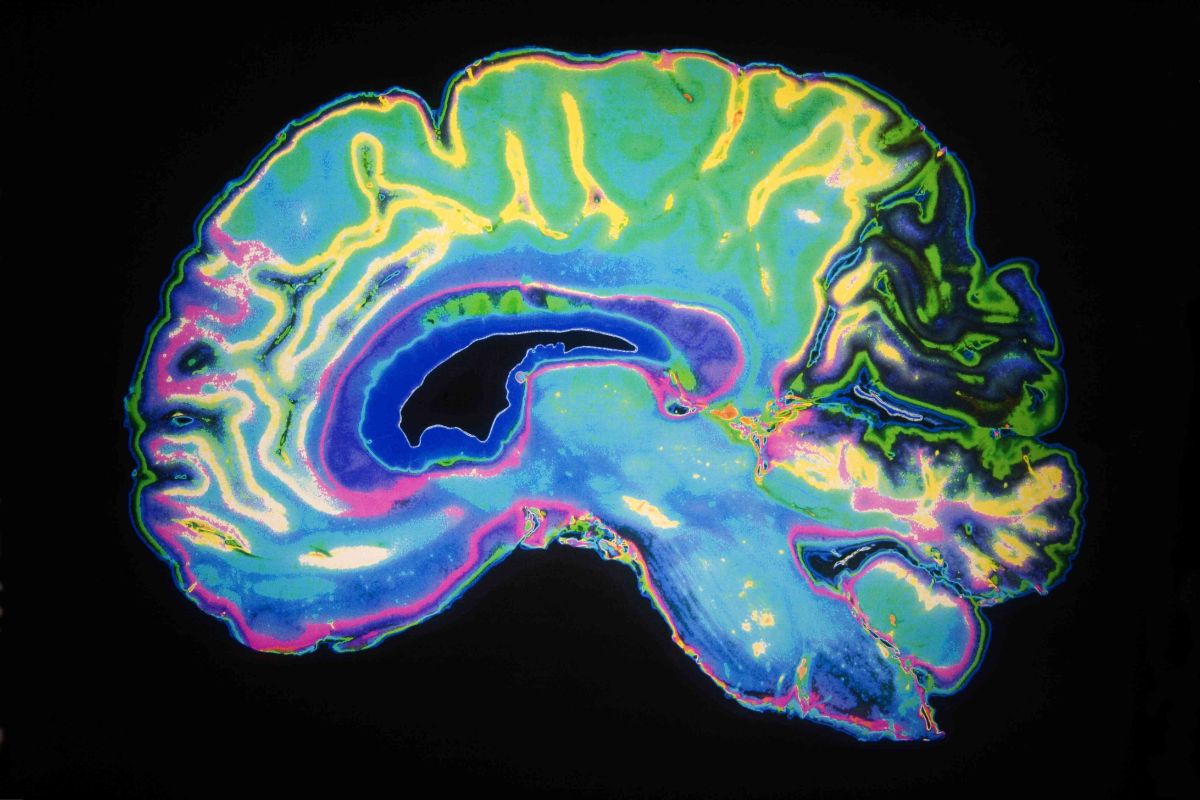

L’idée d’une « cartographie génétique » pouvant être associée aux troubles mentaux remonte au début des années 2010 — c’est-à-dire une carte des gènes impliqués et surtout, de leurs façons de travailler en commun. Mais ce qu’une équipe d’une quinzaine d’institutions a récemment déposé sur le serveur de prépublication MedRxiv, c’est la carte génétique la plus détaillée du cerveau de l’embryon. Assez détaillée pour, disent-ils, révéler des « réseaux » génétiques qui peuvent expliquer un risque accru de développer cinq troubles, dont la schizophrénie, la bipolarité et le trouble de déficit de l’attention avec hyperactivité (TDAH).

La force de leur recherche vient du fait qu’ils ont eu accès aux données génétiques de 654 embryons avortés ou cerveaux de fœtus, provenant d’études antérieures. En se concentrant sur les gènes dont l’expression avait été associée, dans la dernière décennie, à ces cinq troubles mentaux, ils ont pu repérer davantage de « réseaux » génétiques qui se répétaient d’un cerveau à l’autre.

Mais l’intérêt de cette recherche est qu’elle fournit un portrait à la fois plus pointu du problème — on commence désormais à avoir une idée des interactions entre ces gènes, une connaissance qui aurait été hors de portée des technologies d’il y a 20 ans — et plus général : une « architecture génétique » sous-jacente à ces cinq troubles pourrait être en train d’émerger de cette « cartographie ».